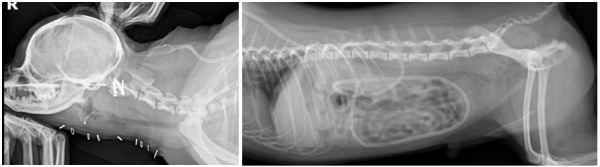

1. VP Shunt (Ventriculoperitoneal Shunt) 삽입

: 과도한 뇌척수액(CSF)을 복강으로 우회 배출시켜 뇌압을 낮추는 수술

2. AAI 고정 수술

: 경추의 불안정 부위를 고정하여 척수 압박을 해소하고 신경 손상을 예방하는 수술

AAI 수술 후 핀과 레진이 삽입된 모습 (좌) , VP shunt 수술 후 복강 내로 카테터가 삽입되어 있는 모습 (우)

→ 수술 후 코코는 약 2~4주간의 회복 기간을 거치며,

보행 이상 증상이 많이 호전되었고,

이전보다 밝고 활발한 성격을 되찾게 되었습니다.